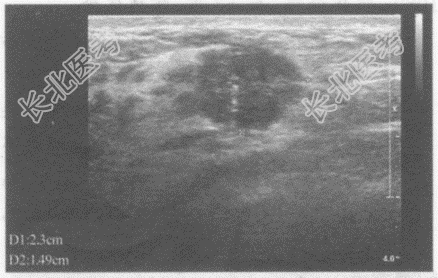

超声综合描述: 右乳外上象限可见2.0cm×1.5cm低回声区,形态欠规则, 边界不平呈锯齿状,内回声不均, 可见点状强回声,CDFI: 内可见较丰富点棒状动静脉血流信号,V

31.0cm/s。见下图及彩图。